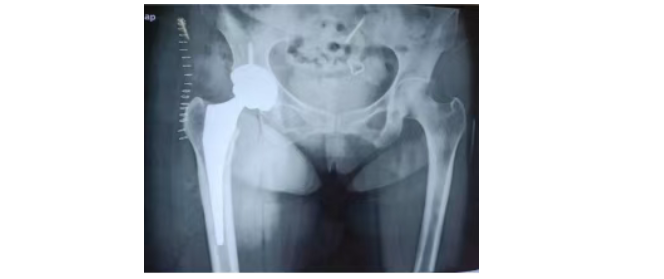

景德镇市第一人民医院骨科关节组袁志峰主任医师团队紧跟前沿技术,在熟练运用常规后外侧入路行髋关节置换的同时,目前科室已常规开展侧卧位DAA微创全髋关节置换术。从术后反馈来看,患者恢复情况良好:术后第一天,患者步态正常,疼痛反应轻;术后一个月复查,同样能实现深蹲,后方关节囊及外旋肌群的保留,大大降低了后脱位风险;肌间隙入路减少肌肉损伤,让患者恢复速度更快,生活质量显著提升。